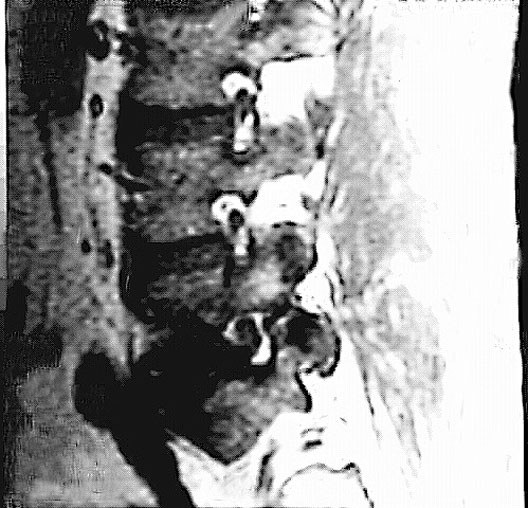

Radiology Images

Lumbar Spine Zoom

1. Spinal nerve in intervertebral foramen

2. Intervertebral disc